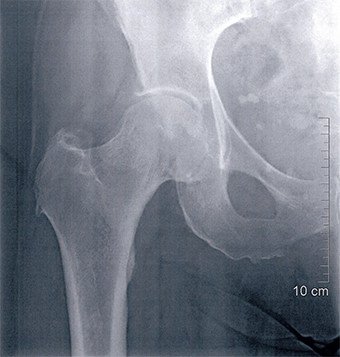

Die klinische Untersuchung und das Röntgenbild zeigten einen spontanen Abriss der Hüftmuskulatur, der sich im Magnetresonanz-Tomogramm bestätigte. Diese Befunde konnten auch bei der Operation verifiziert werden. Der Hüftmuskel war zu 90 Prozent abgerissen und aufgrund Nichtgebrauchs teilweise verfettet. Der Muskel wurde mit starken Fäden wieder an den Knochen angenäht und die Nähte zusätzlich über eine Schraube gesichert. Damit die Muskulatur spannungsfrei anheilen konnte, wurde jeweils der Hüftkopf entfernt. Dies führte zu einer Gehunfähigkeit, weshalb die Patientin die meiste Zeit bis zur Reoperation in einem Rollstuhl verbringen musste.